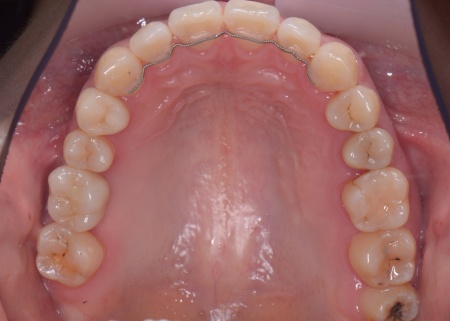

| カウンセリング | 拝見したところ、右上と左下の奥歯に強い痛みが出ていました。 レントゲンで確認した結果、どちらも歯の根が割れていることが判明しました。 歯の根が割れたまま放置すると噛むときの痛みが続くだけでなく、炎症が広がって周囲の歯や骨にまで影響を及ぼすおそれがあります。 また、上下の歯を噛み合わせた際に前歯が噛み合わず隙間ができる開咬(かいこう)と呼ばれる噛み合わせも見られました。 以上のことから、抜歯後に歯を補う治療と噛み合わせを改善するための治療が必要と診断しました。 |

患者様は「健康な歯をできるだけ守りたい」との理由から、③のインプラント治療を希望されました。 まず、右上と左下の奥歯を抜歯しました。 矯正がある程度進んだ段階で、右上と左下のインプラント手術を実施しました。 インプラント手術後は矯正治療の仕上げを行い、装置を外しています。 治療終了後、下前歯の間に見られる三角形のすき間(ブラックトライアングル)が気になるとのご相談がありました。 |